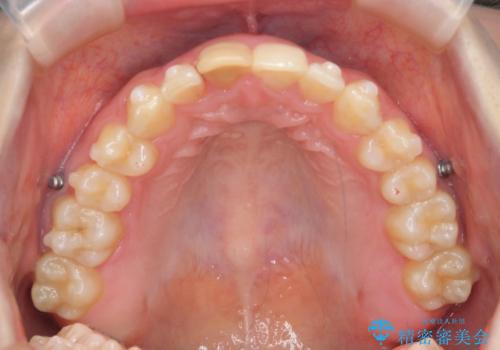

前歯のがたつき 深い噛み合わせを改善したい

- 「前歯のガタつきをきれいにしたい、噛んだ時に下の前歯が見えないことを改善したい」とマウスピース矯正を希望され来院されました。

マウスピースに加え、矯正用マイクロインプラントやゴムを併用し、がたつきや噛み合わせの深さを改善していきます。

ゴムかけやマウスピースの装用時間、しっかりとマウスピースをはめ込むチューウィーをしっかりと使用したことで良好な治療結果を得ることができました。